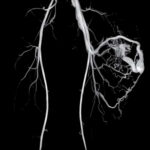

Magnetic Resonance Imaging is a medical imaging technique that uses strong magnetic fields and radio waves to create detailed images of the inside of the body. MRI provides valuable information about the structure and function of organs, tissues, and various parts of the body, making it a powerful tool for diagnosing and monitoring a wide range of medical conditions.

MRI is a versatile imaging technique that can be used to examine various parts of the body, including the brain, spine, joints, abdomen, and pelvis.

It is particularly useful for visualizing soft tissues like organs, muscles, tendons, ligaments, and the central nervous system. Unlike X-rays or CT scans, MRI does not use ionizing radiation, making it a safer option for many patients, including pregnant women and children. MRI is a valuable tool in modern medicine, providing non-invasive and detailed imaging that helps healthcare professionals make accurate diagnoses and develop effective treatment plans for patients.